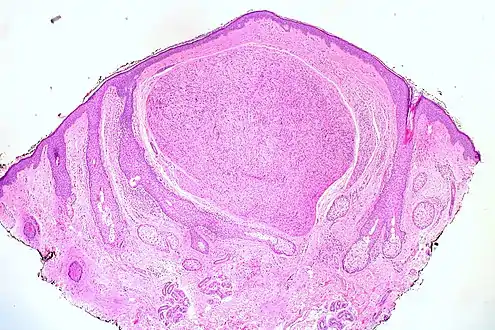

Skin tumors(palisaded encapsulated neuroma)